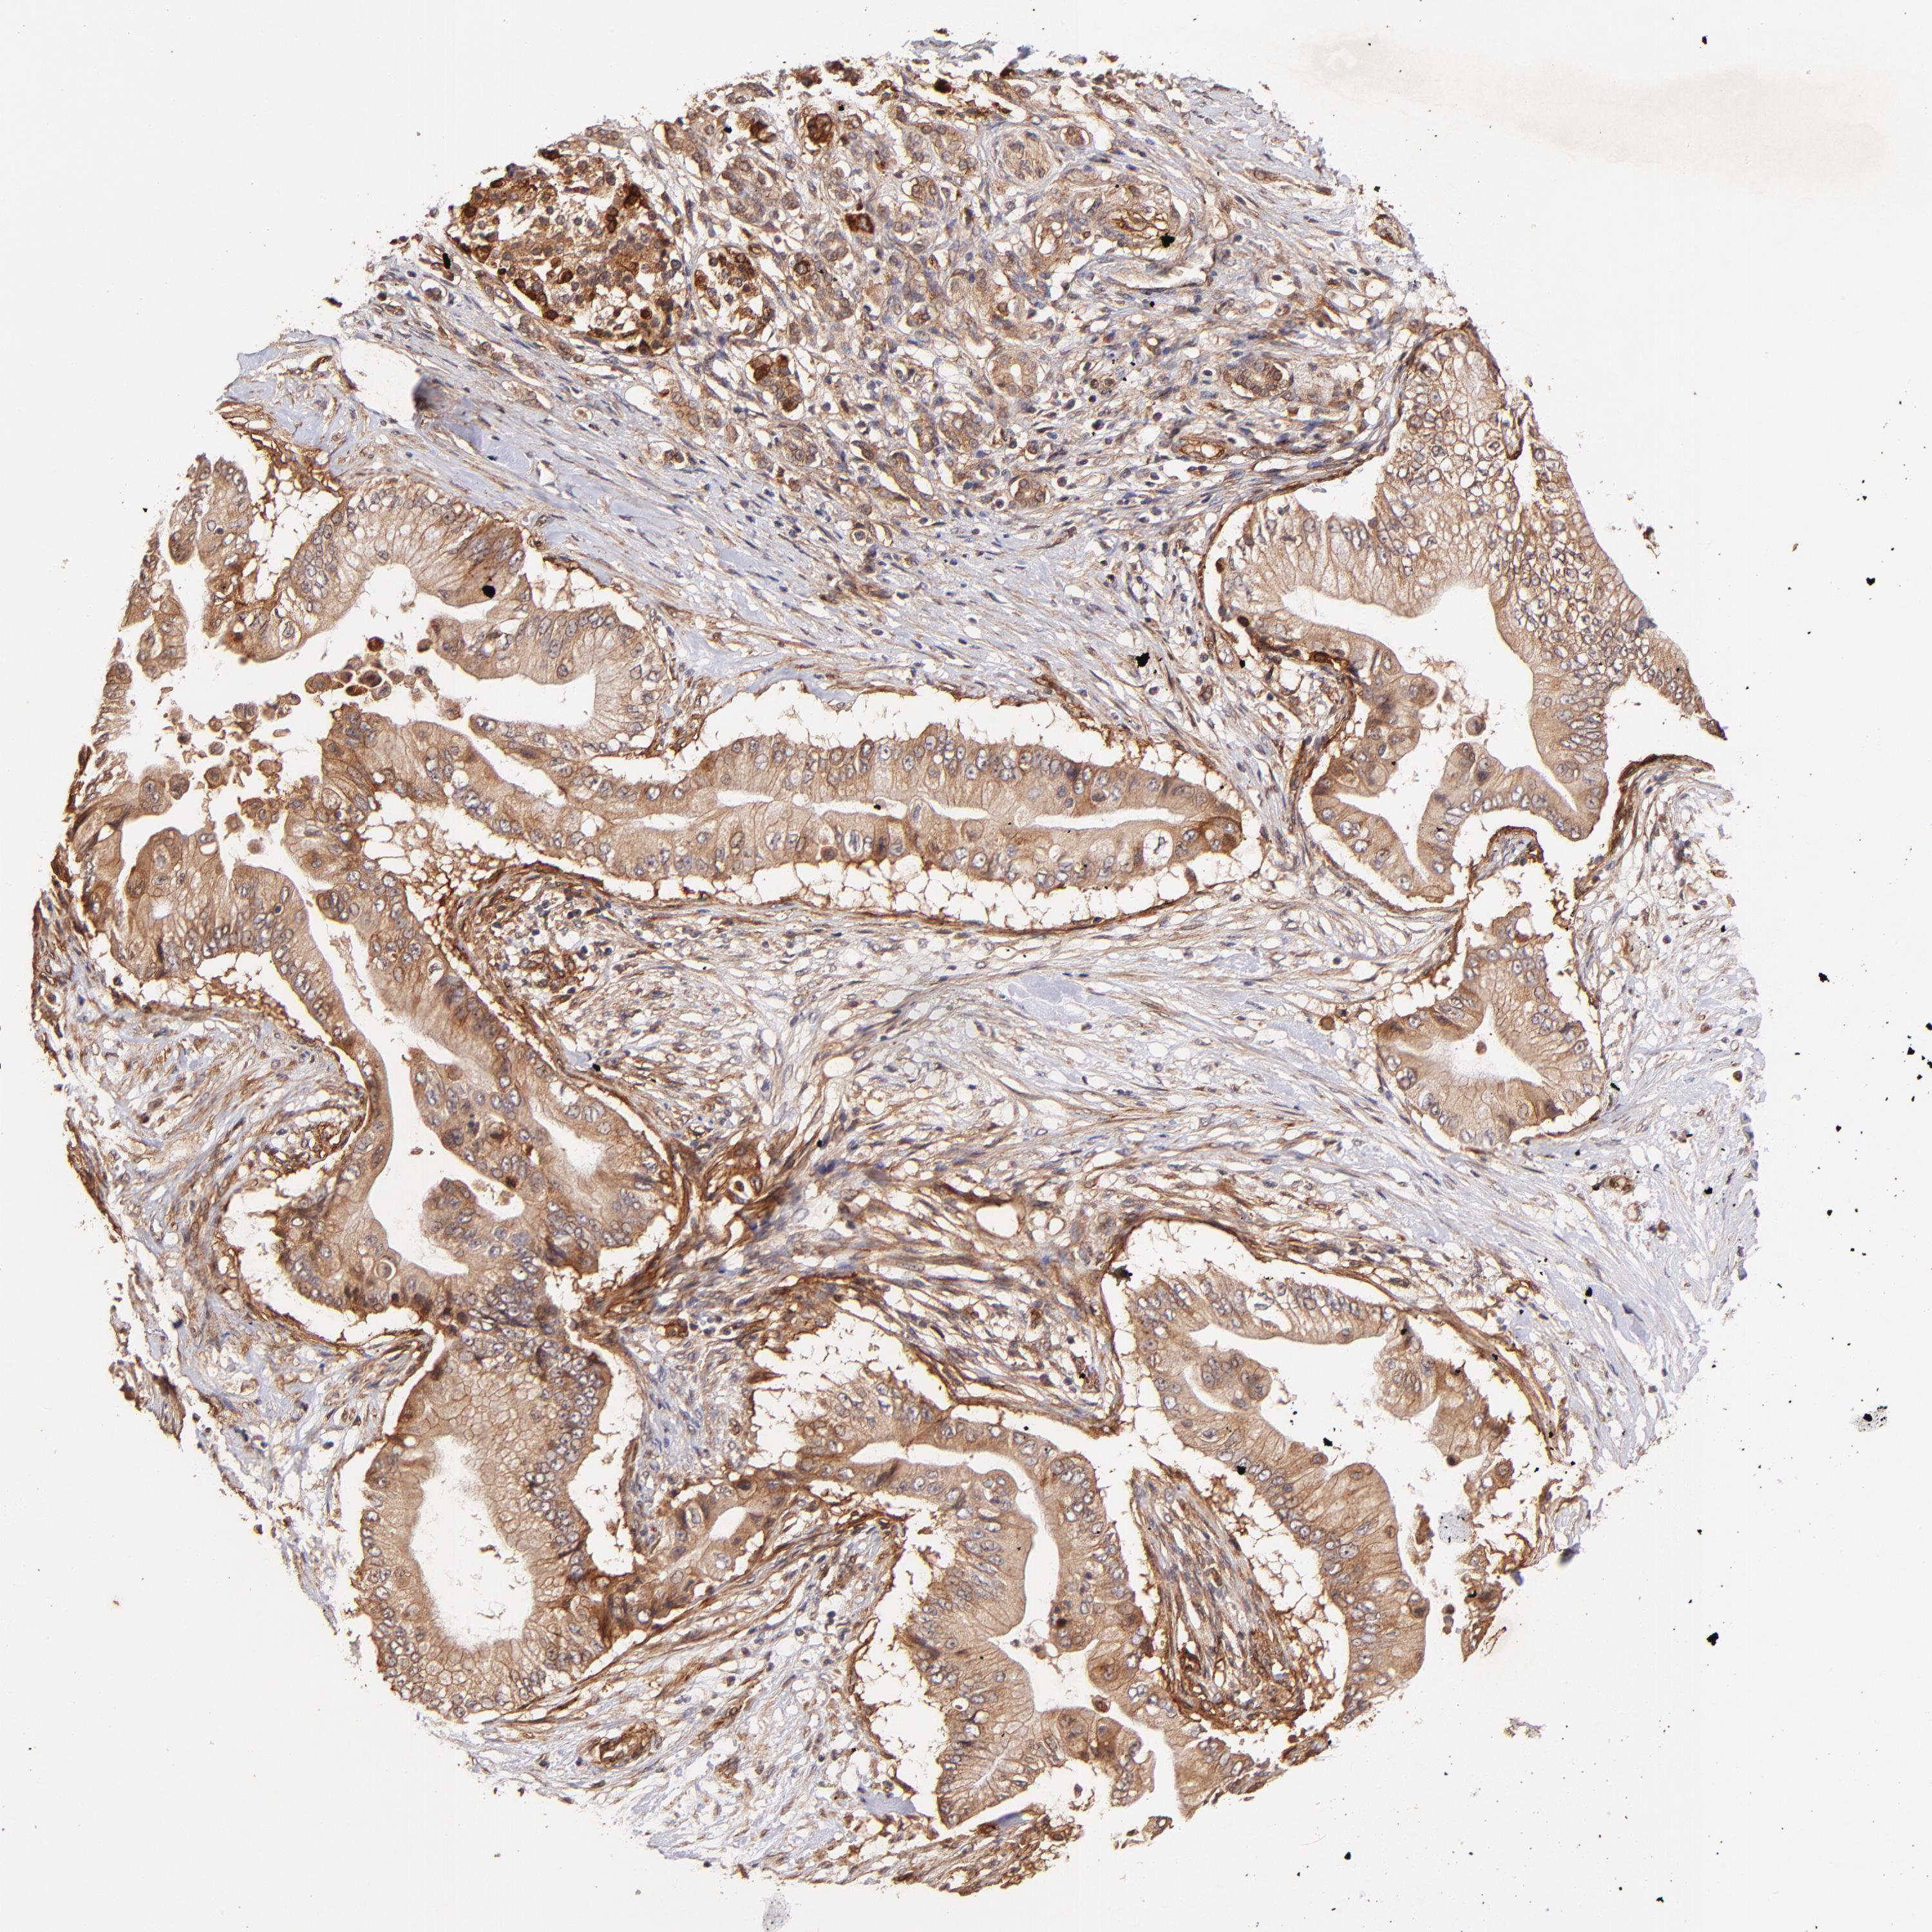

PANCREATIC CANCER - Protein expressioni

A mouse-over function shows sample information and annotation data. Click on an image to view it in a full screen mode. Samples can be filtered based on level of antibody staining by selecting one or several of the following categories: high, medium, low and not detected. The assay and annotation is described here.

Note that samples used for immunohistochemistry by the Human Protein Atlas do not correspond to samples in the TCGA dataset.

Antibody stainingi

Antibody staining in the annotated cell types in the current human tissue is reported as not detected, low, medium, or high, based on conventional immunohistochemistry profiling in selected tissues. This score is based on the combination of the staining intensity and fraction of stained cells.

Each image is clickable and will lead to virtual microscopy that enables deeper exploration of all samples and also displays staining intensity scores, fraction scores and subcellular localization as well as patient and tissue information for each sample.

Antibody HPA059297

Antibody HPA069003

Antibody CAB003434